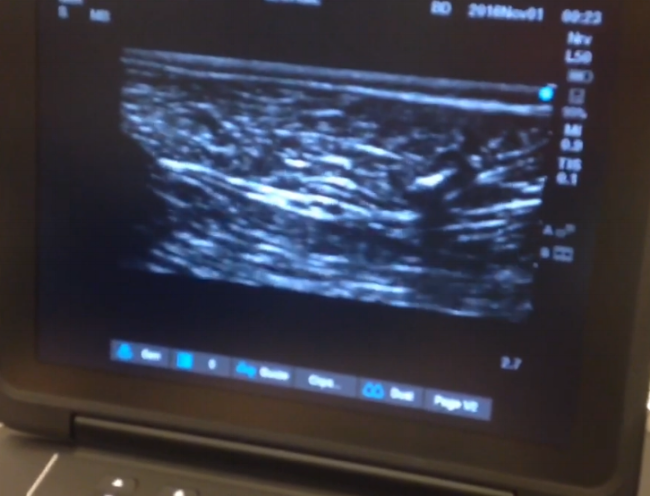

Nerve Blocks, one of the many ways we can keep your patient comfortable

Sciatic nerve block, using ultrasound to visualize the image. The bright white structure running through the middle of the screen is the nerve. The bright white structure to the upper right is the approaching needle. With the femoral nerve block, th…

Sciatic nerve block, using ultrasound to visualize the image. The bright white structure running through the middle of the screen is the nerve. The bright white structure to the upper right is the approaching needle. With the femoral nerve block, this will desensitize the knee for surgery.